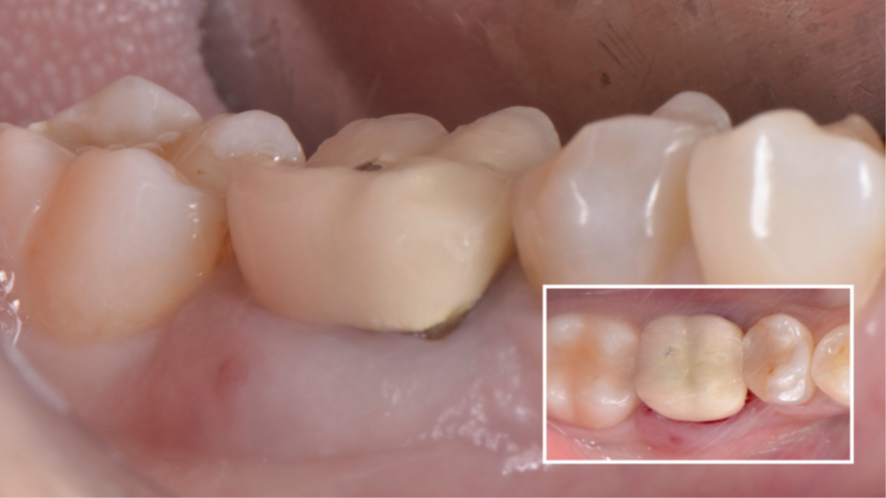

Mulher de 48 anos, sem antecedentes médicos relevantes, procurou atendimento odontológico com queixa principal de dor contínua em região do primeiro molar inferior direito. Na avaliação clínica foi observado uma fístula na vestibular do dente 46 (Figura 1) e a tomografia revelou uma fratura longitudinal, comprometendo a manutenção deste dente (Figura 2). Confirmada a necessidade de exodontia, foi planejada a instalação de um implante imediato e a confecção de um cicatrizador personalizado diretamente na plataforma do implante com um pilar provisório de titânio. Foi realizada uma extração dentária minimamente traumática visando preservar a integridade dos tecidos moles e duros circundantes (Figuras 3 e 4).